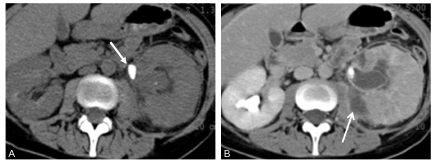

Fig. 27.2. Colique néphrétique en scanner sans injection de produit de contraste iodé : coupe axiale (A) et reconstruction coronale (B).

Calcul de 5 mm bloqué dans l’uretère lombaire (flèche) avec infiltration péri-urétérale et dilatation des cavités excrétrices (∗).

- le scanner sans injection :

- il donne des informations sur la morphologie du calcul (taille et densité), sur sa localisation et sur son caractère unique ou multiple ;

Au scanner sans injection, tous les calculs sont spontanément très denses, supérieurs à 300 UH, avec des densités variant entre 300 UH (cf. figures 27.2 et 27.3) et plus de 1 000 UH, selon leur composition chimique.

En cas de colique néphrétique, le scanner met en évidence une distension de la voie excrétrice supérieure ainsi qu’un œdème de la graisse périrénale et, parfois, un urinome en rapport avec une rupture d’un fornix (bénigne et toujours réversible à la levée de l’obstacle).